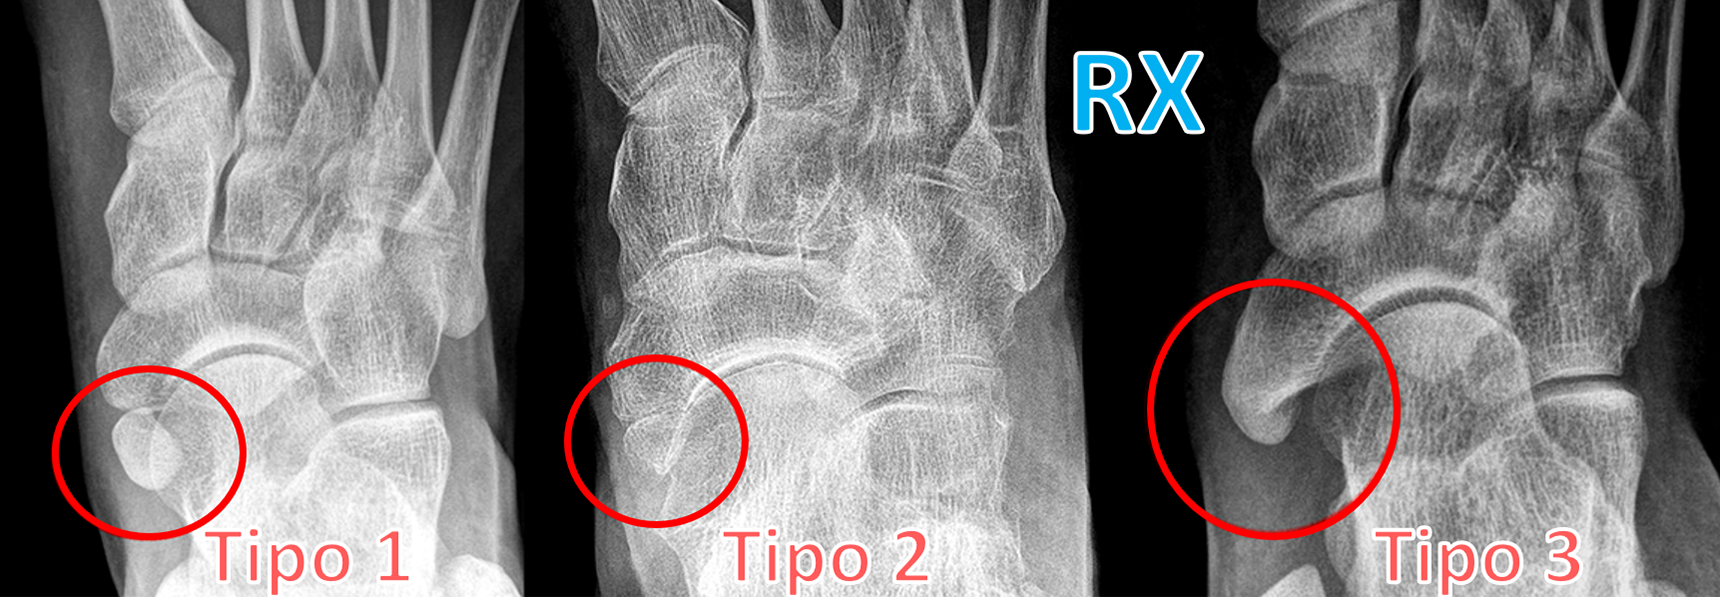

O navicular acessório é classificado em três tipos:

Tipo 1 - Pequeno osso acessório sem conexão ou articulação direta com o corpo do navicular. Normalmente de forma arredondada e bem delimitada, localizado na porção plantar da inserção do tendão tibial posterior. Assintomático na maioria dos casos.

Tipo 2 - Porção óssea claramente relacionada com o corpo do navicular, separada por uma placa fibrocartilaginosa (sincondrose). Frequentemente causa sintomas dolorosos, principalmente após atividade física.

O navicular tipo 2 Pode estar localizado medialmente, na ponta da tuberosidade e sujeito à força de tração pelo tendão tibial posterior (Tipo 2A), ou mais plantar, abaixo do navicular e sujeito à força de cisalhamento pelo mesmo tendão (Tipo 2B).

Tipo 3 - Prolongamento ósseo da tuberosidade do navicular. O osso acessório está unido por uma ponte óssea rígida e contínua, dando um formato mais alongado ao navicular.